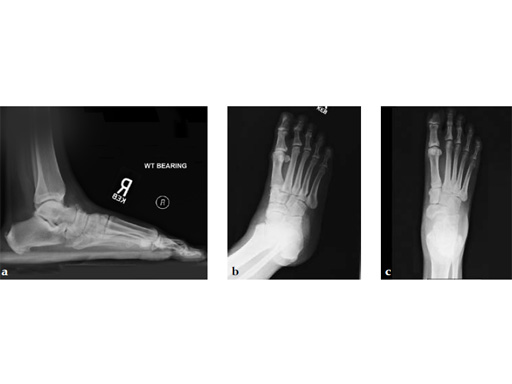

Case 3: First TMT fusion plate

A 48-year-old woman, with hallus valgus and hypermobile medial column, also resulting in pes plano abductovalgus (flatfoot).

Case provided by Andrew Sands, New York, New York, USA

Surgery consisted of first TMT and intertarsal corrective osteotomy plus fusion with movement of the first MT lateral and plantar. This corrects the hallus valgus as well as the PPAV (and stabilizes the medial column).